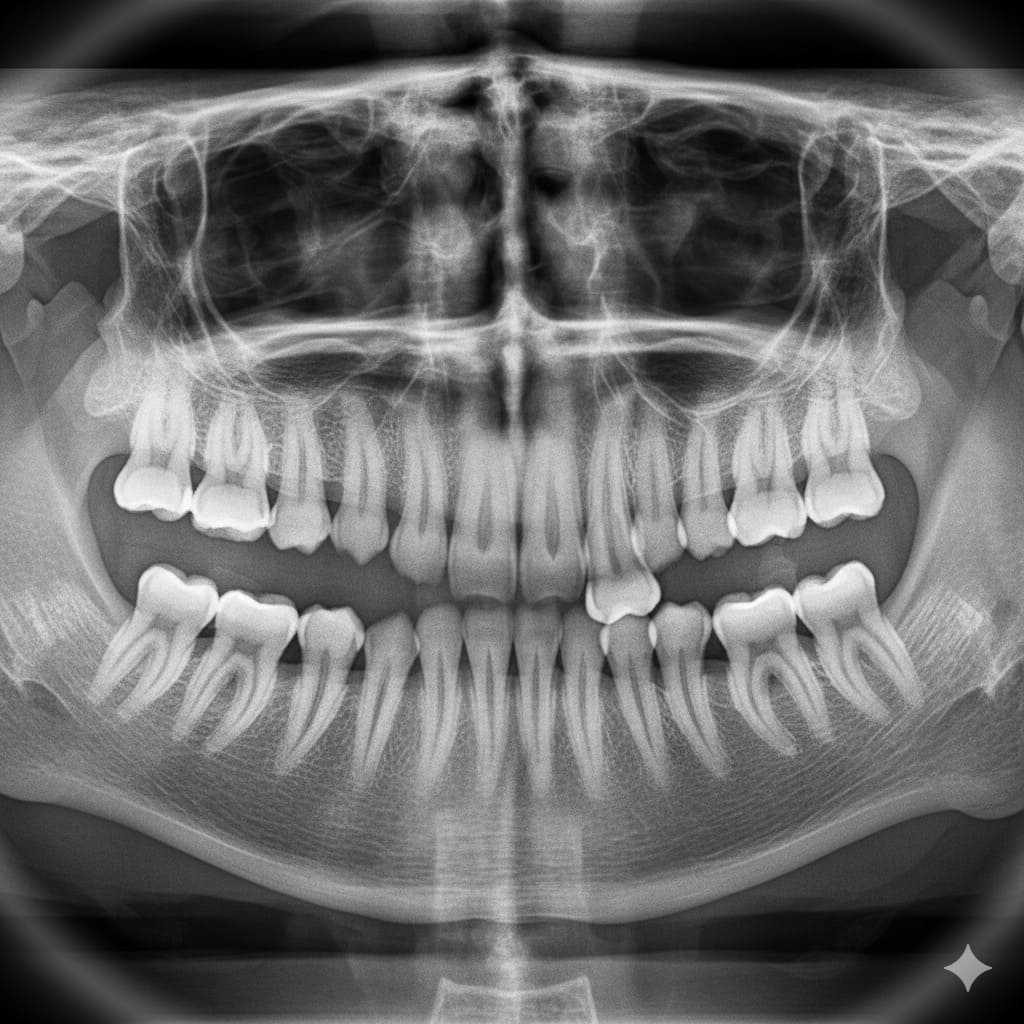

Las muelas del juicio, también conocidas como terceros molares, suelen aparecer entre los 17 y los 25 años. Son las últimas en salir y muchas veces no tienen suficiente espacio en la boca para erupcionar correctamente.